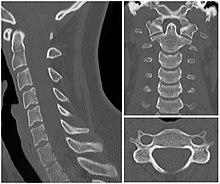

Axial skeleton and extremities

For the axial skeleton and extremities, CT is often used to image complex fractures, especially ones around joints, because of its ability to reconstruct the area of interest in multiple planes. Fractures, ligamentous injuries, and dislocations can easily be recognised with a 0.2 mm resolution.[41][42] With modern dual-energy CT scanners, new areas of use have been established, such as aiding in the diagnosis of gout.[43]